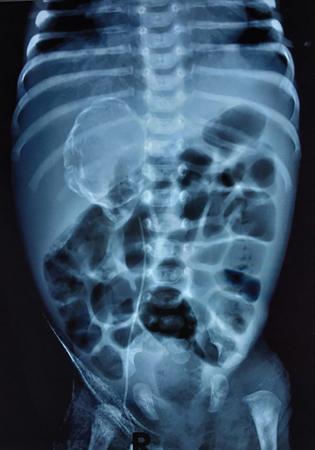

Various abdominal calcifications can be seen on the scout film and need to be differentiated from renal calcifications. They include gallbladder calculi which appear as multiple faceted calcifications in the right upper quadrant, calcific chronic pancreatitis which is seen as multiple stippled calcifications in the upper abdomen adjacent to the lumbar spine, adrenal or hepatic calcifications appear as stippled and discrete calcifications overlying the right twelfth rib. Renal calculus is seen as separate deposits of calcified density confined to the renal shadow. Other calcifications within the renal shadow include cortical and medullary nephrocalcinosis (Figs. 10.6.2 and 10.6.3). Stippled suprarenal calcification in a paediatric patient may point towards a neuroblastoma while rim calcification may be seen in a case of adrenal haemorrhage (Fig. 10.6.4). Calcifications seen in the pelvis can point towards a bladder calculus, ureteric calculus, phlebolith or an intrauterine copper device, calcified fibroid or dermoid cyst in a female patient.

Image

Fig. 10.6.4 A well-defined rounded lesion with peripheral rim calcification in the right hypochondrium in an infant with perinatal adrenal haemorrhage which has now calcified.